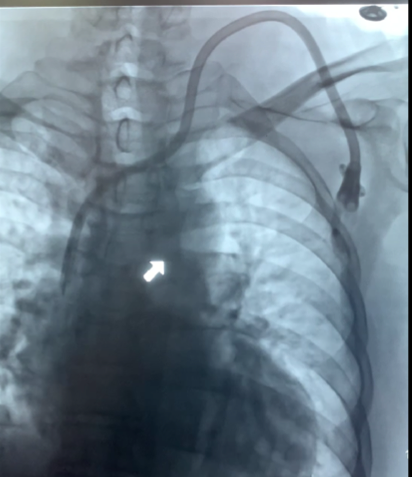

Accesos vasculares: inserción de catéter diálisis

Construcción de fistulas para diálisis, complicaciones

Complicaciones de fistulas